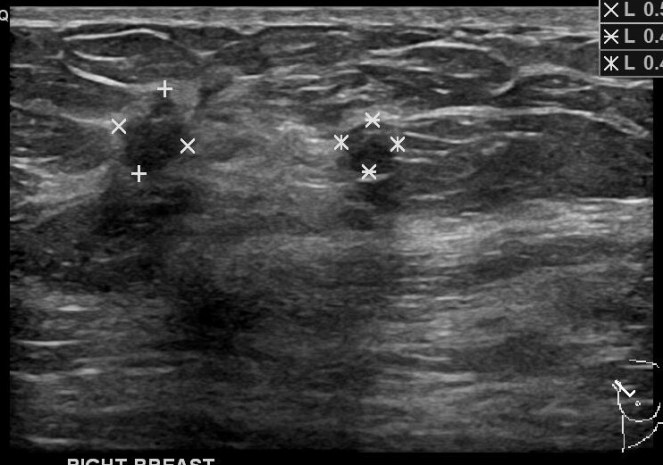

I rested awkwardly on the gurney in the radiology exam room. The radiology nurse had just finished propping me onto pillows and supports to get the angle just right for my impending breast biopsy. She explained the procedure to me, and showed me the teeny tiny titanium markers that would be placed into my breast at the biopsy sites — yes I said “sites”; they were doing two biopsies side-to-side.

This was a culmination of sorts. I’d had my first ever mammogram at age 38 due to a family history of breast cancer, and also very dense breast tissue that was difficult to examine manually. That first mammogram was uneventful, but a few years later I had one where they called me back for a follow-up ultrasound. Then a year later the same thing happened. Finally, in September of 2015, after getting called back for another ultrasound of my right breast, they asked me to come back in six months instead of the usual one year. So earlier this month, on April 11, I had a mammogram followed by an immediate ultrasound. The U/S technician was wanding me over and over in the same place, near my armpit on Righty, for a solid twenty minutes, while I held my iPhone (yes, reading my book) in my left hand; and my right hand, stretched up uncomfortably over my head (this would become a theme), slowly went to sleep. After that U/S was done, I was told that there were multiple “shadows” that they needed more information about. I needed to come back for a biopsy.